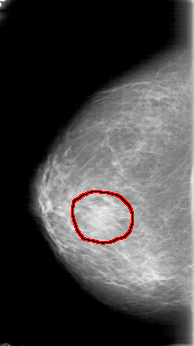

FILE: D_4023_1.RIGHT_MLO.OVERLAY

TOTAL_ABNORMALITIES 1

ABNORMALITY 1

LESION_TYPE MASS SHAPE OVAL MARGINS OBSCURED

ASSESSMENT 0

SUBTLETY 2

PATHOLOGY BENIGN

TOTAL_OUTLINES 1

BOUNDARY